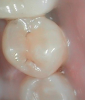

Fig 4. Open-tooth camera photograph confirmed caries exactly where it was displayed on transillumination image.

Figure 4

Figure 1 shows a pretreatment photograph of a tooth No. 20. In Figure 2, the circled area of the x-ray indicates the interproximal area where the clinician was uncertain if caries was present. Though x-rays are useful, transillumination is more sensitive and optimal for detecting caries in the early stages.12 With new devices, clinicians can acquire more information before working on the tooth. As shown in Figure 3, caries was confirmed using the transillumination system (CariVu), though it did not show up on an x-ray. The clinician was able to show the image to the patient. The open-tooth camera image then revealed the extent of the caries in the exact position that was displayed in the transillumination image (Figure 4). This is a significant advantage in minimizing preparations and saving valuable tooth structure.